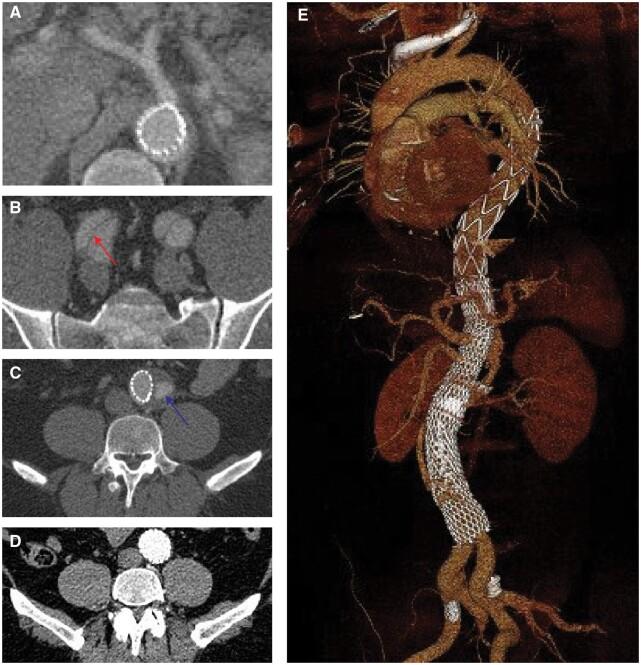

The goal of this study was to describe the factors affecting mid and late aortic remodelling following thoracic endovascular aortic repair with the PETTICOAT (Provisional Extension To Induce Complete Attachment) technique among patients with complicated acute or subacute type B aortic dissection.

A retrospective single-centre study that evaluates clinical and morphological outcomes among 65 consecutive patients. The area and diameter of the true and false lumen, overall aortic diameter and false lumen perfusion were evaluated.

Concomitant direct visceral artery stenting was successfully conducted in 32 (49%) patients. There was one (1.5%) postoperative stroke; three (4.6%) patients developed spinal cord ischaemia; two (3%) patients suffered retrograde type A dissection; and two (3%) patients had mesenteric ischaemia, despite successful reperfusion, that required a bowel resection. Median postoperative follow-up was 63.1 (interquartile range, 32.1- 91.8) months. The probability of survival was 96.9% [95% confidence interval (CI) 88.3%-99.2%] at 30 days, 93.9% (95% CI 84.4%-97.6%) at 1 year, 78.0 (95% CI 64.2%-87.0%) at 5 years and 72.8% (95% CI at 57.9%-83.2%) at 10 years postoperatively. There was a statistically significant postoperative increase in true-lumen area, diameter and true-lumen index in all five aortic levels measured. Complete false lumen (FL) thrombosis at the coeliac trunk, renal arteries and aortic bifurcation levels was observed in 47%, 15% and 24% of patients at midterm (6-15 months) and in 29%, 21% and 29% on late (later than 21 months) computed tomography angiograms (CTA). Persistent false lumen (FL) perfusion at the coeliac level on midterm CTA was associated with a larger extent of late aortic growth (P = 0.042) and was, in the majority of cases, caused by iliac re-entries either alone (28.57) or in combination with visceral and lumbar (28.57%) or distal aortic (10.71%) re-entries. A larger abdominal aortic diameter at midterm was associated with an increased probability of distal aortic reinterventions (hazard ratio 7.26, 95% CI 2.41-21.9, P < 0.001).

Persistent FL perfusion of the distal aorta at midterm following TEVAR with the PETTICOAT technique among patients with acute and subacute type B dissection is caused mainly by iliac, visceral, lumber and distal aorta re-entries. Patients with persistent FL perfusion have an increased risk of aortic aneurysmal growth at late follow-up.